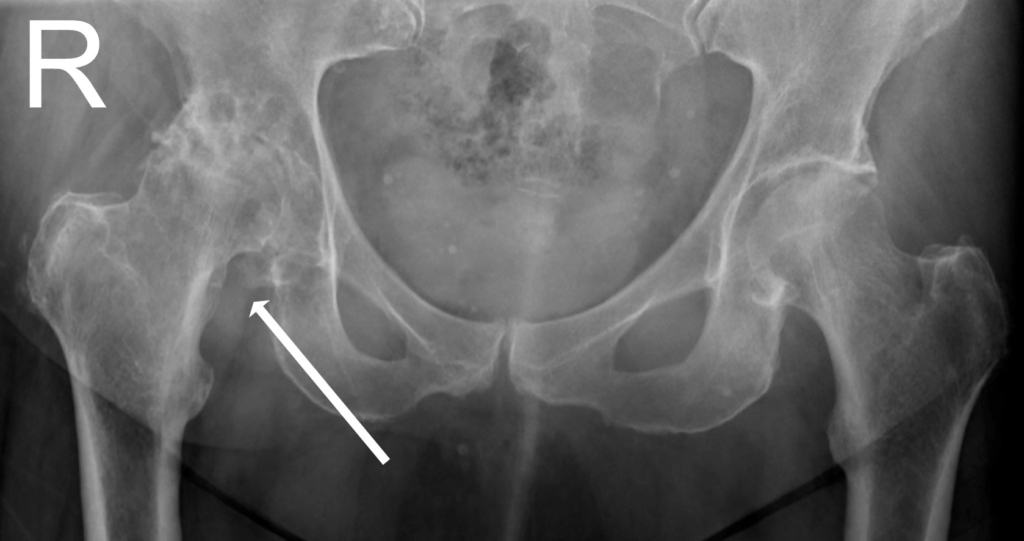

Chẩn đoán chính xác bệnh viêm khớp háng

Tiến sĩ Clohisy và các đồng nghiệp của ông là những chuyên gia về bệnh viêm khớp háng. Đánh giá chẩn đoán có thể sẽ bao gồm những điều sau:

- Tiền sử bệnh của bạn, bao gồm cả vị trí bị đau và có dấu hiệu đi khập khiễng

- Đặc biệt là khám sức khỏe để xem bạn cử động hông có tốt không?

- Chụp X quang để xác định xem có bất kỳ bất thường nào ở khớp hay không

- Xét nghiệm máu để xác định kháng thể có thể liên quan đến một loại viêm khớp cụ thể (chỉ khi cần thiết).